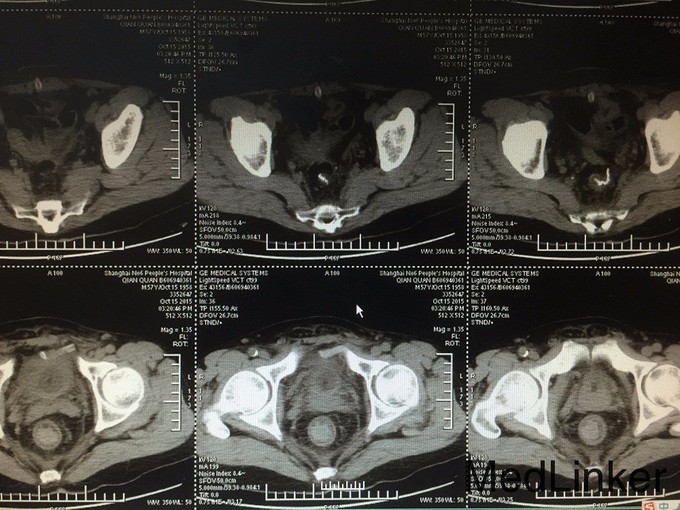

患者,男,57岁,因“突发腹痛4天,伴停止排气排便2天”来院就诊。 病史:患者于4天前出现腹部胀痛,为阵发性钝痛;无面色苍白,无出冷汗,无放射痛,无恶心,有呕吐,为胃内容物,2天来肛门停止排便,排气,在当地医院就诊,查腹部CT提示腹腔内肠管内多个液平面,腹腔积液,直肠于乙状结肠连接处可见缩窄占位性改变,当地医院建议手术治疗,后患者选择转我院进一步诊治,我院急诊查血常规:血常规示WBC:6.9*10^9/L,N:73.8%,红细胞 4.74X10^12/L,血红蛋白 141g/L,血小板 154X10^9/L,急诊收治入院。

查体:神志尚清,腹膨,全腹部散在轻压痛,无反跳痛,无肌卫,未见其余特殊查体发现。 辅查:血常规示WBC:6.9*10^9/L,N:73.8%,红细胞 4.74X10^12/L,血红蛋白 141g/L,血小板 154X10^9/L。肝肾功能、电解质:血清钾(干式) 3.7 mmol/L ,血清钠(干式) 136 mmol/L ↓,血清氯(干式) 98 mmol/L ,总蛋白(干式) 56 g/L ↓,白蛋白(干式) 33 g/L ↓,谷丙转氨酶(干式) 41 U/L ,谷草转氨酶(干式) 20 U/L ,尿素(干式) 9.2 mmol/L ↑,肌酐(干式) 68 μmol/L 。免疫检验报告:梅毒螺旋体特异抗体 阴性 ,梅毒血清反应素 阴性 ,HIV抗体 阴性 。肿瘤指标:糖类抗原(CA199) 31.21 U/mL ↑,神经元特异烯醇化酶 20.65 ug/L ↑,其余指标正常。外院腹部CT:腹腔内肠管内多个液平面,腹腔积液,直肠于乙状结肠连接处可见缩窄占位性改变。

入院诊断:急性肠梗阻、直肠恶性肿瘤。 治疗:患者入院后急诊行“剖腹探查+直肠癌切除+远端封闭+乙状结肠造口术(Hartmann术)“。术中探查发现腹腔中量腹水,吸尽腹腔积液后探查及腹膜返折上5cm直肠处可及一肿块,质硬,占肠腔一圈,活动尚可,已浸润至直肠浆膜层。肿块近端结肠及小肠扩张伴肠壁明显水肿增厚,肠系膜、肝脏、胃、腹壁等无转移性结节。行直肠肿瘤切除+乙结肠造瘘术。 手术经过顺利,术后标本送病检,病人安返病房。术后予对症支持治疗,术后复查腹部CT提示:直肠术后,左下腹造瘘后,腹腔引流中,肠腔少量积气。前列腺密度不均匀,局部见钙化,未见明显增大,两侧精囊未见明显异常,膀胱充盈可,盆腔未见明显肿大淋巴结,盆腔未见明显积液。1.直肠术后,请结合临床随访。2.前列腺钙化。术后造瘘口通畅,恢复进食后顺利出院,术后患者的病理分期为:T3N1CM0 IIIB期。术后诊断为:直肠癌伴肠梗阻(T3N1CM0 IIIB期)。 PS:术后病理报告为—直肠 标本类型:直肠切除标本 肿瘤部位:切除肠管全长13.5CM,肿瘤位于 :距一侧切缘1CM ,距另一侧切缘10.5CM,大小 2 ×1.8CM 大体类型:隆起型,肿瘤环绕肠壁:全周 组织学类型:腺癌 II级 浸润深度达:浆膜外组织 淋巴管内癌浸润:(-),血管内癌浸润:(-),神经周围癌浸润:(+) 切缘:上下切缘均未见癌浸润 区域淋巴结: 以下未见癌转移:淋巴结0/8枚 见癌结节2枚。 淋巴结免疫反应状态:SH(+),PH(+),GH(+) 癌周间质反应:淋巴细胞,浆细胞,组织细胞反应(+),纤维组织增生反应(+) 非肿瘤区病变:粘膜慢性炎症(直肠):腺癌II级,侵及浆膜外脂肪组织。送检组织免疫酶标记结果:CK7(-),CK20(+),Villin(+),CEA(+),CDX-2(+),Ki-67(70%+),D2-40(-),MLH1(+),MSH6(+),MSH2(+),PMS2(+)。